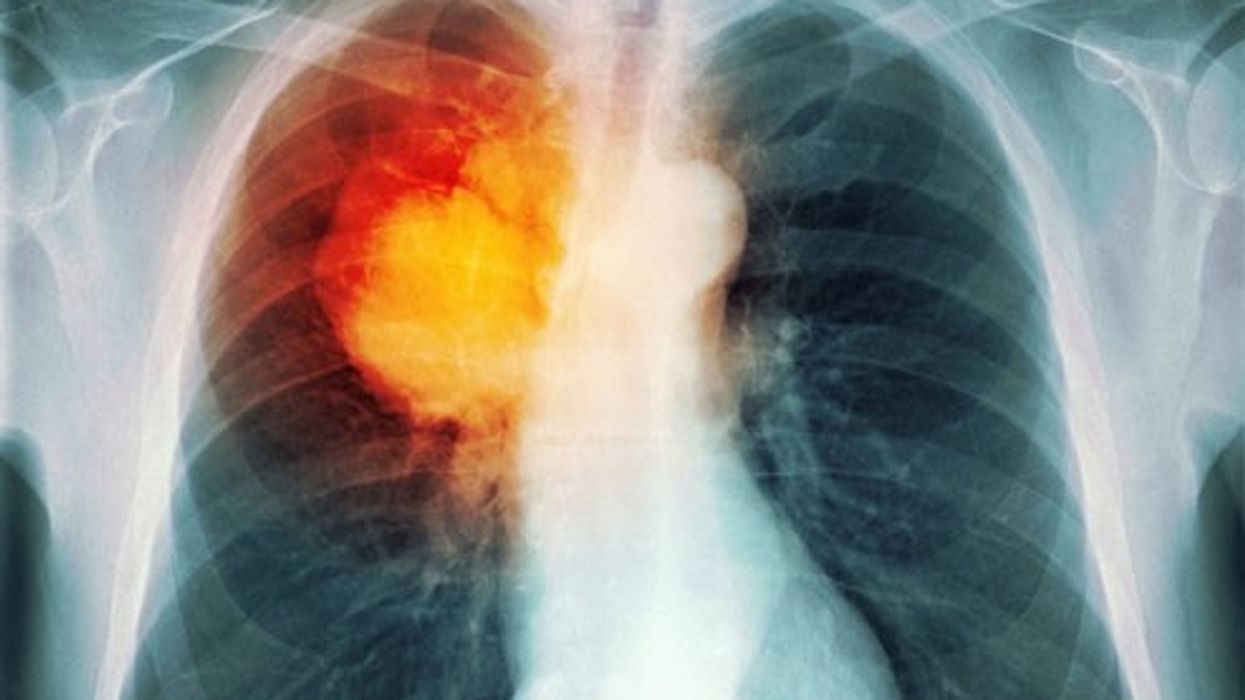

A e rrisin vitaminat e zakonshëm rrezikun e kancerit në mushkëri

Meshkujt, dhe veçanërisht meshkujt duhanpirës, duket se janë më të prirë të diagnostikohen me kancer të mushkërive nëse konsumojnë doza të mëdha të vitaminës B6 dhe B12.